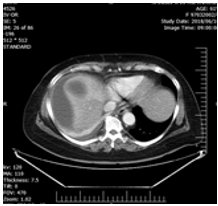

In treatment history, a shoulder Pain was present which not associated with any trauma or GI tract problem. That time she was conscious, only complaining of severe shoulder pain and mild abdominal pain. The shoulder movement was normal. The only physical finding was mild tenderness and guarding in all quadrants of the abdomen. Her blood pressure120/80 mmHg, heart rate was 95 beats min, respiratory rate 18 bpm, WBC=21000. Three days after admission, she had a CXR showed that shoulder joint was normal but in chest mild pleural effusion and atelectasis was present with on the right side. The patient underwent ultrasonography which showed one intact cystic lesion (42x38mm) in the left lobe and two cysts in the right lobe (87x83mm) and (67x4 mm) and computed tomography of abdomen showed as U&S but showed fluid at sub diaphragmatic location and around with on liver (Figures 1-3).

Figure 3: CT-scan of patient show two cystic lesion in the right lobe, which one is completed ruptured and one left lobes with effusion in around the liver.